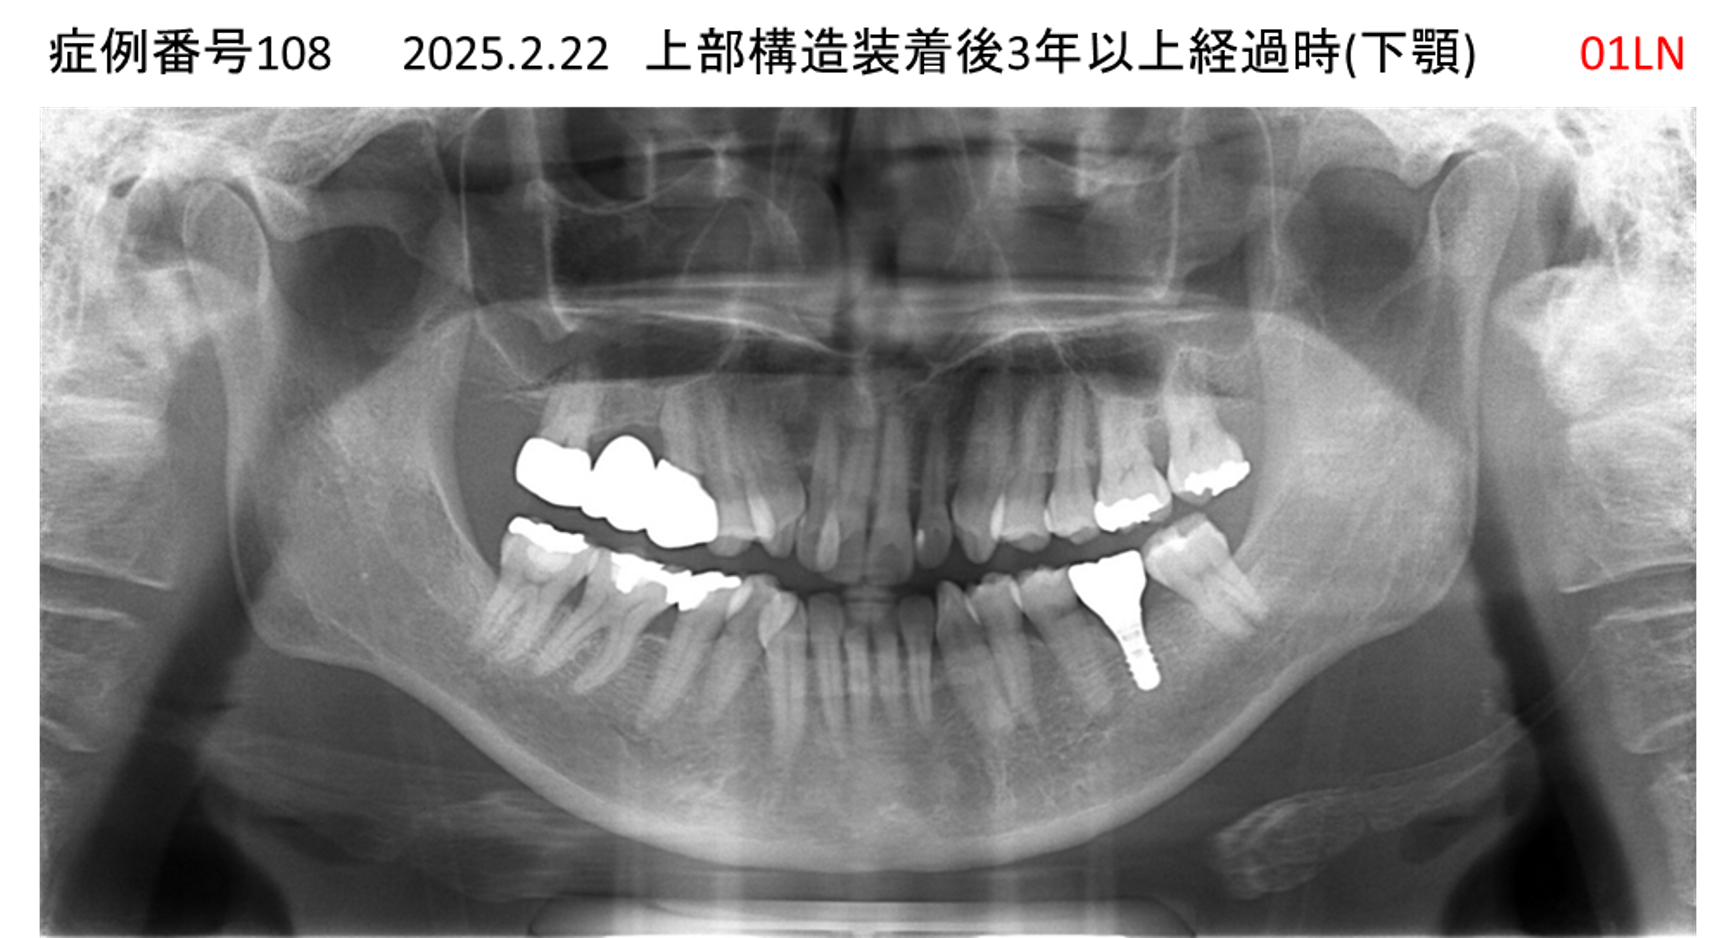

奥歯で噛めない患者様のインプラント症例

| 治療名称 |

インプラント |

| 治療費用 |

365万円+税 |

| 治療期間 |

5か月 |

| 患者さんの症状(主訴) |

奥歯で噛めない。上の前歯が揺れてきた。 |

| 治療内容 |

抜歯即時インプラント |

| 治療結果 |

食事に困らない。見た目がとても良くなった。 |

| 治療の注意点(リスク/副作用) |

インプラントが壊れたら再治療が必要 |